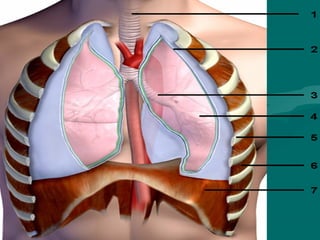

AnatomiaAnatomia